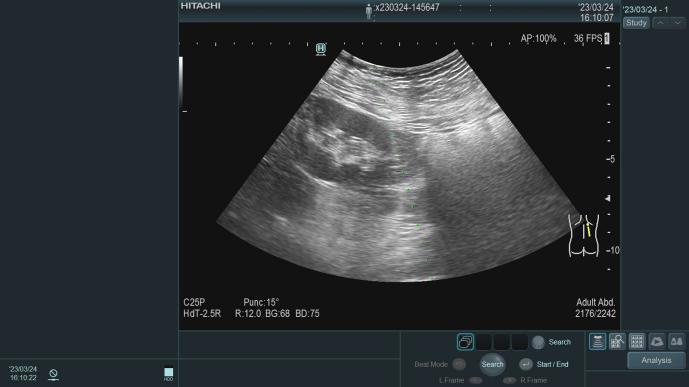

一、延缓肾脏病进展的综合治疗在广西较早独立编制的肾脏病专业科室,1995年开始应用超声引导下经皮肾穿刺活检术,协助诊断治疗各类肾脏疾病,积累丰富临床经验,如:急性肾小球肾炎、慢性肾小球肾炎、急性肾损伤、慢性肾衰竭、肾病综合征、IgA肾病、狼疮性肾炎、ANCA相关性小血管炎、糖尿病肾病、高血压肾病等疾病的诊断及治疗。难治性肾病综合征是常见的肾脏疾病,在长期临床实践中,积累了丰富的诊治经验。通过应用甲基强的松龙冲击、环磷酰胺、环孢素等治疗方法,同时开展生物制剂(利妥昔单抗等),应用先进的多靶点免疫抑制治疗诊治多种难治性肾病综合征,诊疗水平达到区内先进水平。肾穿刺活检术在重症肾脏疾病诊治方面,建立专职医护团队,对重症系统性红斑狼疮、血管炎...